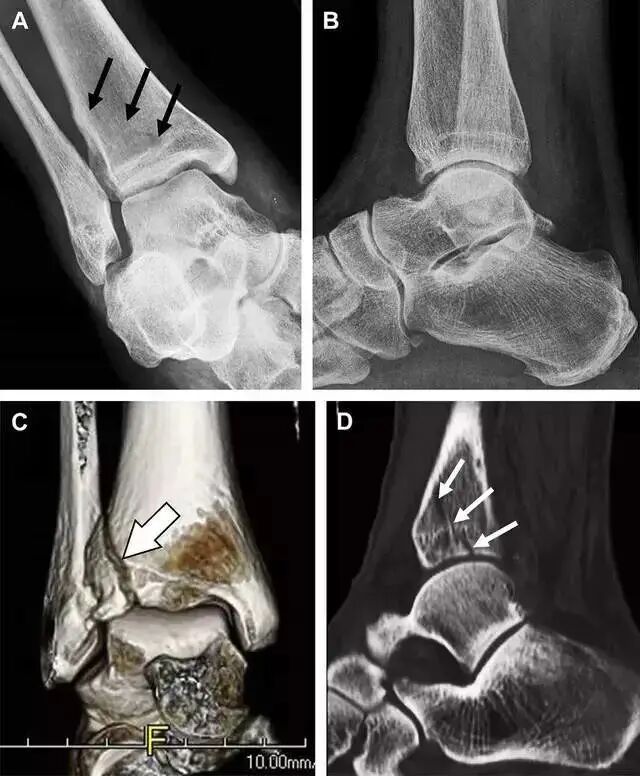

胫骨后踝骨折

涉及到三角韧带和外侧副韧带(LCL)的复杂性骨折常常不难发现,尤其是存在表面软组织肿胀时。然而,后胫腓韧带牵拉引起的胫骨后踝骨折则很难发现。这些骨折大小不一(图 2),却很重要,因为他们常与胫骨远端螺旋骨折有关,或者是三踝骨折的一部分。

图 2 胫骨后踝骨折。A 侧位片示来源于胫骨后踝的一个小骨折碎片(箭头),因踝部扭伤导致;B 另一位跖屈损伤的患者,侧位片示一个大骨折块(箭头)

胫骨结节骨折

Tillaux 骨折,是足外旋外展时,胫腓前韧带牵拉引起的一种胫骨结节撕脱性骨折。斜位片上可见典型表现(图 3)。

图 3 摔倒后胫骨结节骨折。A 正位片示一细小斜型骨折线(箭头);B 侧位片示正常;C 冠状位 CT 三维成像更清晰地显示了骨折线和骨折块大小(空箭头);D 矢状位 CT 多维重建图像示骨折位置(箭头)

距骨外侧突骨折

距骨外侧突骨折常因踝外翻背屈时,跟骨上外侧面撞击距骨外侧突下缘导致,或偶尔由踝内翻引起,被称为「滑雪板者骨折」。这种骨折只能在踝关节正位片上发现,而且外踝远端表面软组织肿胀往往是一个重要线索(图 4)。

图 4 距骨外侧突骨折。A 正位片示内翻损伤所致的距骨外侧突撕脱性骨折(箭头);B 另一位患者,踝外翻损伤导致典型的「滑雪板者骨折」,X 片上可见一较大的三角形骨折块(方框);C 第二位患者的 MRI 矢状位 T1 加权像示横行骨折(箭头)